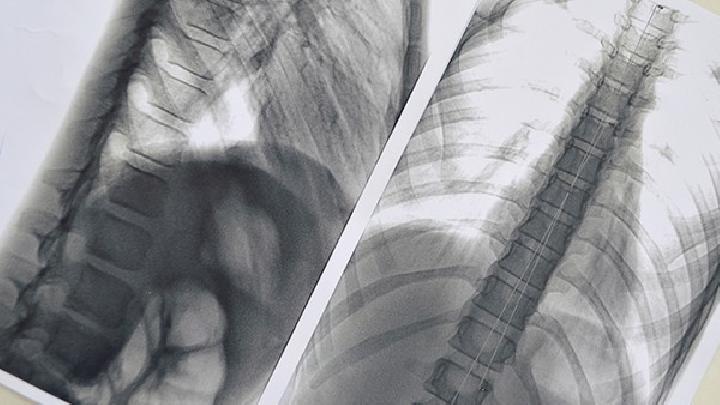

皮肤癌最有效的检查

活检病理检查,对皮肤癌的分类,以及治疗方法也极其重要,而且治疗效果也不同。 皮肤癌的常见检查有体格检查、血常规检查、免疫功能检查、病理学检查、X射线检查、B超检查、CT检查、核素检查等。 皮肤癌包括基底细胞癌、鳞状细胞癌、恶性黑色素瘤、恶性淋巴瘤、特发性出血性肉瘤(Kaposi肉瘤)、汗腺癌、隆突性皮肤纤维肉瘤、血管肉瘤等。 1)基底细胞癌:真皮内有边界明显的瘤细胞群,胞核较正常稍大,呈卵形或长形,胞浆少,细胞间界限不清,细胞间无间 2)鳞状细胞癌:癌细胞成团块或条索增生侵入真皮内,其中有多少不等的正常和不典型分化不全的鳞状细胞及角化不良细胞。 3)以上是对皮肤癌疾病的检查项目进行较为详细的介绍,我们对皮肤癌疾病的检查有一个比较完整的认识,当身体出现异常时,一定要到正规的医院进行详细的检查,从而避免疾病对我们造成危害。 关于细胞的信息![]() 小细胞肺癌日常护理注意事项?不知道你们是否了解小细胞肺癌疾病呢,它让我们感觉到很痛苦害怕,不及时治疗的话,可能会影响生命,那么今天我们一起来看看,小细胞肺癌日常护理注意事项? ![]() 小儿急性淋巴细胞白血病的病因是什么呢?小儿本应该成长的无忧无虑,但是白血病的出现不仅仅让孩子们饱受疾病的折磨,还给整个家庭造成了不可估计的伤害,那么到底是什么样的原因造成了小儿患上了急性淋巴细胞白血病呢? ![]() 小细胞肺癌是不是吃药就可以?因为小细胞肺癌比较特殊在我们生活不算非常常见,但是肺癌的发生却是小细胞肺癌渐渐发生发展的结果,所以治疗好小细胞肺癌非常重要,一定不要因为不了解而不重视,以为随便吃点药就能解决,那样是不对的,那么小细胞肺癌是不是吃药就可以呢?下面我们就来聊一聊这个问题。 ![]() 治疗小细胞肺癌的价钱高不高?现在由于各种不正规医院的出现,很多人对于医院都产生了极大的不信任,患有小细胞肺癌想去医院治疗,但是又怕价钱太高,那么今天我们一起来了解一下,治疗小细胞肺癌的价钱高不高? ![]() 小细胞肺癌的危害通常有哪些呢?对于小细胞肺癌听着就非常恐怖的一种疾病,很多的人都因为没有及时的治疗导致生命走到终点,所以在发现的时候要尽早的治疗,但是这个疾病到底有什么危害呢?下面我们一起来了解下吧! ![]() 应用骨髓间充质干细胞治疗自身免疫性重症肌无力研究在哈尔滨医科大学取得新突破,为重症肌无力患者的临床治疗提供了实验基础和理论依据。这一最新研究成果近期发表于德国国际期刊《欧洲免疫学》、美国国际期刊《神经免疫学》和英国国际期刊《免疫学》上。 ![]() 一提起小细胞癌很多患者并不了解,有的甚至都没听说过这个名字,更别提对它的了解了,小细胞癌对人们的危害很大,所以对于小细胞肺癌患者一定要做到早发现早治疗,如发现一些小细胞肺癌的症状就及时去检查避免耽误病情,那么小细胞肺癌的症状有哪些呢?下面我们一起来了解。 ![]() 小细胞肺癌如何防治?小细胞肺癌的死亡率是很高的,常见的原因是早期因无症状表现而发现困难,当发现症状到医院就诊时,已进展到了晚期,今天我们一起来看看,小细胞肺癌如何防治: ![]() 急性淋巴细胞白血病怎么检查呢?患上了急性淋巴细胞白血病之后,通过检查才可以及时的进行诊断和治疗,而检查也是对于疾病治疗的过程中不可缺少的一个重要部分,因此我们一定要注意这一点才行,那么急性淋巴细胞白血病怎么检查呢? ![]() 小细胞肺癌用什么药好呢?任何的疾病都是在早期的治疗效果才更好,但是对于这个疾病很多人想选择吃药治疗,但是不知道哪种药物效果明显,下面我们一起来了解下小细胞肺癌用什么药好吧! ![]() 小细胞肺癌初期症状有哪些呢?对于小细胞肺癌大多数人都非常的陌生,但是在近几年来这个疾病的发病在不断的提高,很多人都想提前的预防,但是不知道是什么症状,下面我们一起了解下小细胞肺癌初期症状有哪些吧! |